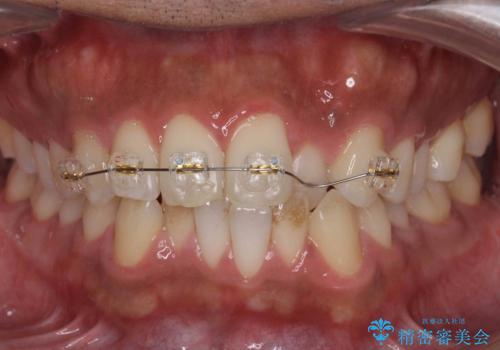

前歯が反対にかんでいる 部分ワイヤーとインビザラインの併用で短期治療

前歯が一本奥に入っているのを乗り越えるにはワイヤー矯正が治療期間も短く、歯に負担が少なく有利と説明しました。

上はワイヤー部分矯正、下はインビザラインの部分矯正コースを行いました。

また、入れ替えを行う間左上の前歯だけで咬まなくてはならない状況になるため、マウスピース矯正単独で行うと時間がかかり、最悪神経が失活することもありますのでワイヤーがお勧めです。